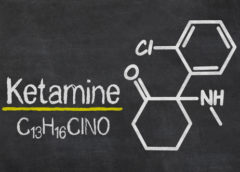

LeggiDolore acuto infantile: ketamina intranasale efficace quanto il fentanyl

Nei bambini con traumi acuti a carico delle estremità la ketamina intranasale risulta non inferiore al fentanyl nell’alleviare il dolore. Secondo Theresa Frey del Cincinnati Children’s Hospital Medical Center, autrice dello studio PRIME condotto su 85 bambini che ha portato a queste conclusioni, è…